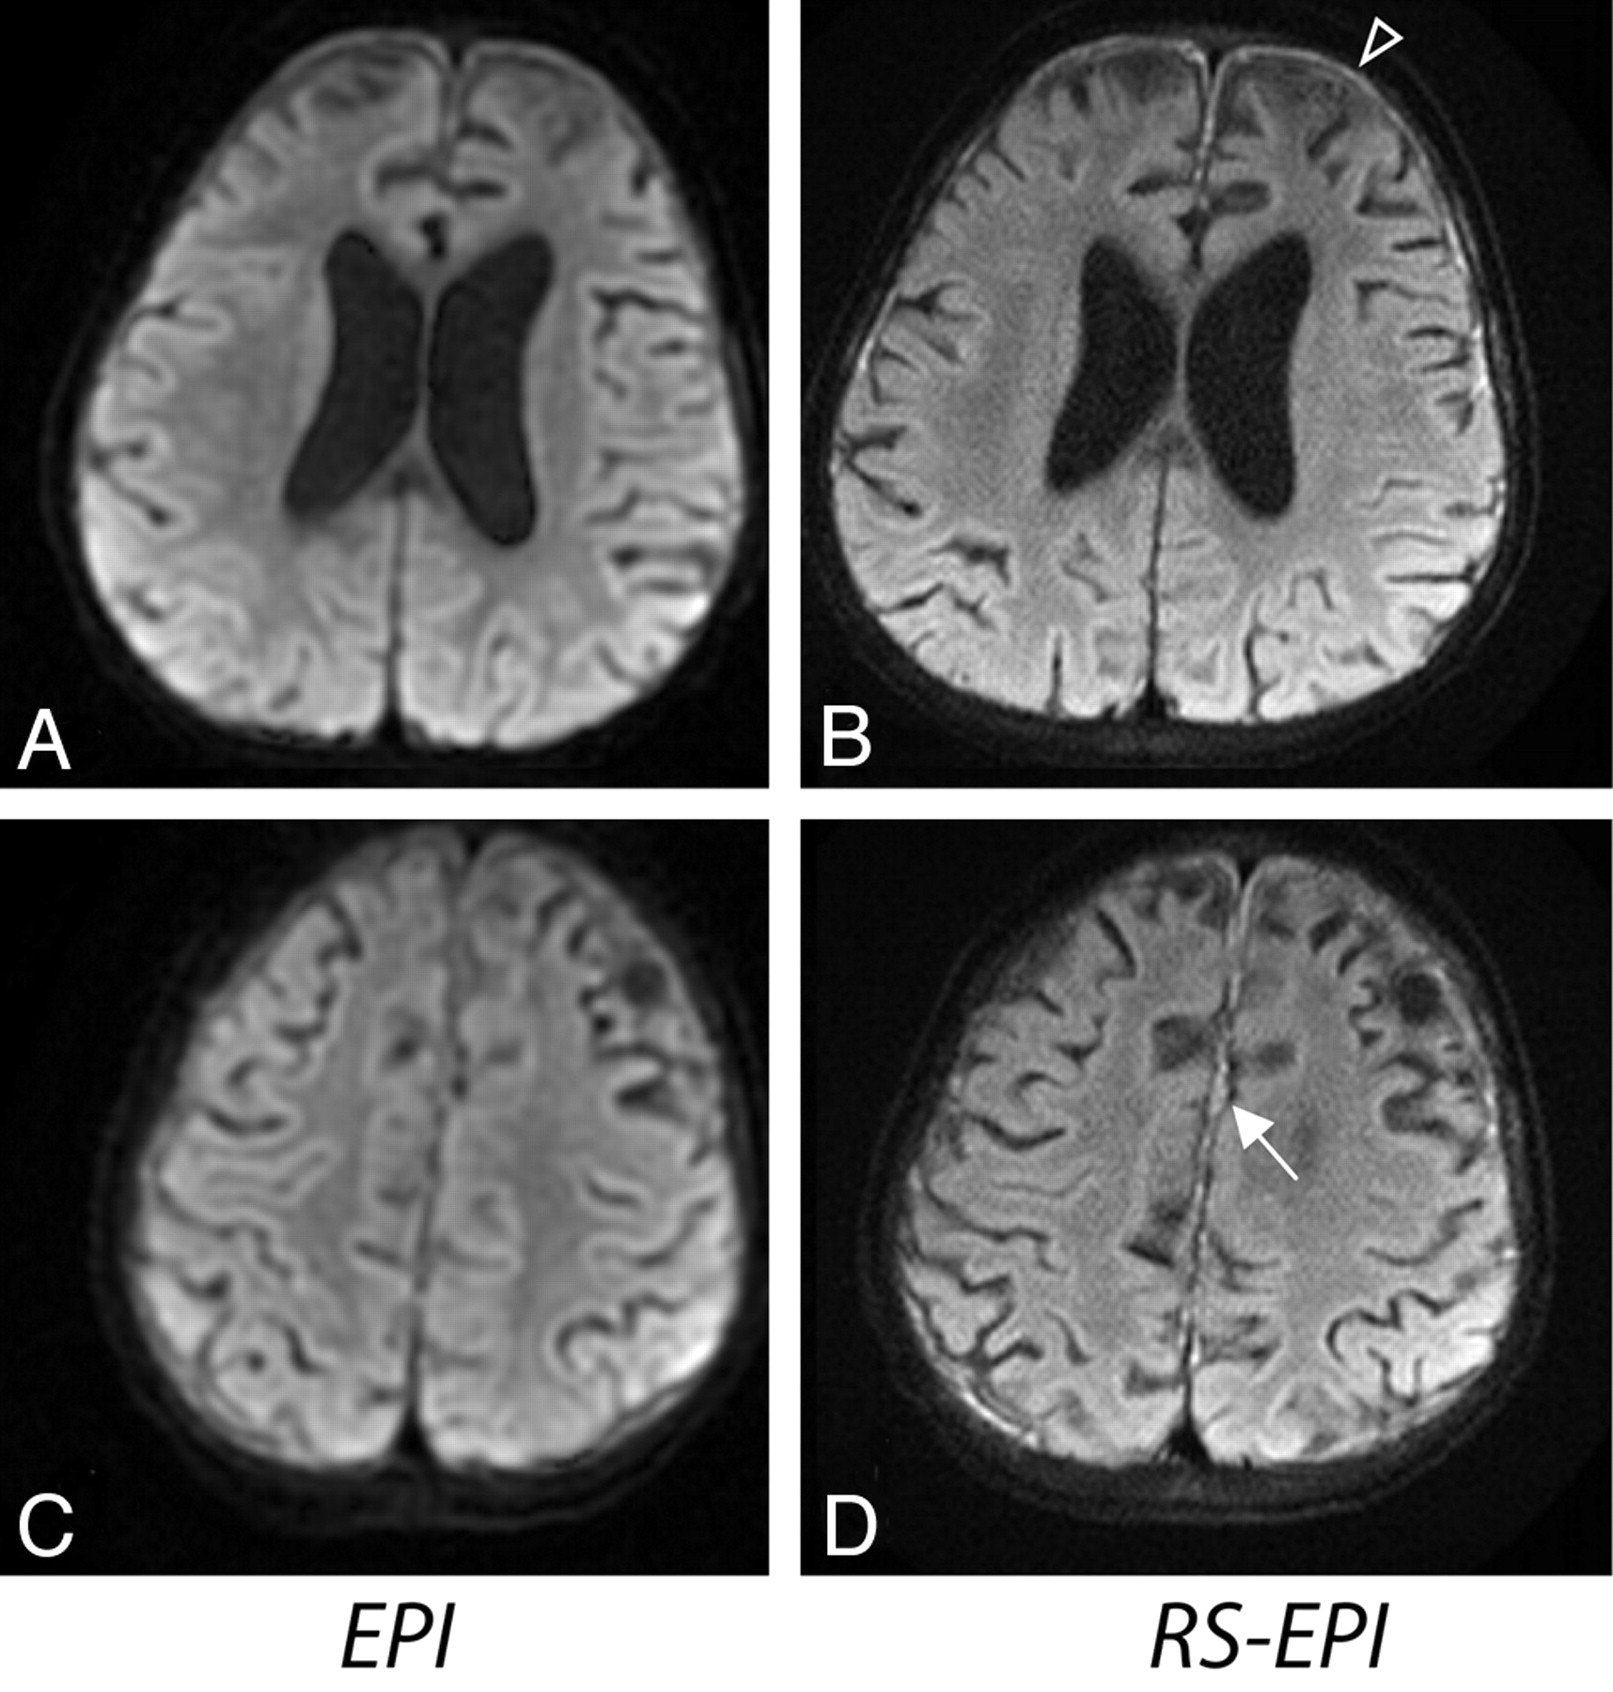

The average scores calculated across 35 patients are shown in Fig 2. The following scores were given to EPI, RS-EPI, and RS-EPI re-evaluated alongside the EPI, respectively: resolution, 3.5/5.8/5.2; distortion level, 2.9/5.5/6.0; SNR, 3.4/4.2/4.1; lesion conspicuity, 3.3/6.0/5.9; and diagnostic confidence, 3.2/5.8/6.0. The P values for EPI versus RS-EPI viewed first independently and then as a direct comparison, were as follows: resolution, 1.9 × 10−6/1.2 × 10−6; distortion level, 1.3 × 10−6/9.5 × 10−7; SNR, .006/.007; lesion conspicuity, .005/.007; and diagnostic confidence, 1.3 × 10−6/1.9 × 10−6. Overall, the RS-EPI had significantly improved diagnostic confidence. RS-EPI identified a lesion not found by EPI in 1 patient (a small subdural empyema, Fig 3) and more accurately defined the extent and location of the lesions, such as ischemic injury, metabolic disorder (Fig 4), a cystic encephalomalacia (Fig 5), and a skull base tumor. In 1 case, RS-EPI (Fig 6B) correctly identified a false-positive ischemic lesion in the temporal lobe seen on EPI in a patient with Moyamoya disease (Fig 6A). In another case, RS-EPI (Fig 6D) correctly identified a false-negative ischemic lesion in the temporal lobe in a postoperative patient with Moyamoya disease, where this was presumed to be a post-operative blood-product artifact on EPI. (Fig 6C).

An 18-month-old boy presenting with subdural empyema. A and B, Abscess depicted with greater diagnostic confidence on RS-EPI. C and D, Pus present along the falx on RS-EPI (D), not well seen on EPI (C).

A 10-month-old boy presenting with cystic encephalomalacia. RS-EPI demonstrates cystic encephalomalacic changes with higher resolution.

RS-EPI also reduced distortion in areas adjacent to tissue-air or bone interfaces from signal-intensity pile-up effects (Fig 6A, -B) and gave increased diagnostic confidence in areas adjacent to the auditory canal in a patient with tumor (Fig 7). In several patients, EPI had elevated gray/white matter contrast on iso-DWI due to a more pronounced T2 shinethrough effect from the longer TE of EPI as shown in Fig 8 (note that this did not occur for RS-EPI even though RS-EPI used twice-refocused diffusion preparation which prolongs TE). These equivocal signal-intensity high intensities occasionally led to a decreased diagnostic confidence level.